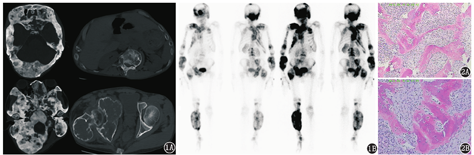

患者男,30岁,近10余年躯体右侧相继出现无痛性包块并逐渐增大。近来患者出现右小腿包块无明显诱因破溃出血近7 h,于外院急诊局部加压包扎止血。右小腿CT提示:右胫骨中段占位,考虑为动脉瘤样骨囊肿?骨纤维异常增殖症?后以"全身多发占位"转入本院。入院体格检查:枕部隆起畸形,质硬、不活动、边界欠清晰;右侧身体多处扪及质硬、不活动、边界欠清晰包块,无明显压痛;脊柱侧弯畸形,无明显叩击痛;右小腿石膏外固定,增粗明显,周径约40 cm,局部见一大小约0.5 cm窦口,皮温增高明显,无明显出血。全身淋巴结未扪及明显肿大。辅助检查:WBC计数11.20(括号中为正常参考值范围,下同;3.50~9.50)×109/L,中性粒细胞计数10.30(1.80~6.30)×109/L,碱性磷酸酶(alkaline phosphatase, ALP) 1 369.20(45.00~125.00) U/L。X线片和CT提示:颅骨、多个腰椎椎体及躯体右侧多发骨质膨胀性、"磨玻璃"样改变,部分区域见多发囊状密度减低区(图1A)。全身骨显像提示:颅骨、脊柱、右侧肩胛骨、双侧肋骨、右侧髋骨、右侧肢体骨多处见显像剂异常浓聚(图1B)。行多部位穿刺活组织检查,病理诊断为骨纤维结构不良(fibrous dysplasia of bone, FDB;图2)。

FDB临床并不罕见,但本例迁延10余年,病灶广泛多发,相对少见。FDB骨显像在早期发现及筛查解剖成像检查范围以外的病灶、与其他骨骼疾病的鉴别、直观显示病骨累及范围及活组织检查部位的选择、疗效评价方面有其自身优势[2],因此广泛应用于临床。因病骨内含有大量未成熟的骨纤维,FDB骨显像多表现为病骨放射性摄取异常增高,可呈干、条索或块状摄取;如病骨范围较大,局部可见放射性分布不均匀改变,受累长骨病灶多见沿骨长轴分布的放射性异常摄取。一般来说,单骨型FDB患者以四肢骨受累多见,多骨型FDB患者所有骨骼均可受累,以颅骨、四肢骨受累多见,颅骨表现为块状放射性浓聚影,并见膨胀畸形。四肢骨病灶多数位于躯体一侧,不超过身体中线[3];超过身体中线者,以一侧受累明显。累及躯干病变可波及数根肋骨和椎体,肋骨不限于身体一侧[4]。本例均可见典型的上述多骨型FDB骨显像表现,但关于FDB在骨显像中骨形是否增大尚有争议[5,6],本例骨显像可见多处长骨梭形膨大,这可能与疾病渐进性发展时间较长有关。对于单骨型FDB,SPECT/CT融合显像可将全身骨显像对FDB的高灵敏度与CT显示病灶的精细结构及骨质破坏特点相结合,大大提高了骨显像的诊断效能[7]。本例右小腿包块破溃处局部皮温增高明显,WBC计数及中性粒细胞计数增高,ALP增高明显。综合临床资料分析:可能因患者病情进行性发展10余年,包块增大明显而致破溃出血,局部感染炎性病变致皮温增高。另有文献报道对于临床ALP升高的部分FDB患者,可用ALP水平评估其病变活动度及作为治疗反应的参考指标[8]。